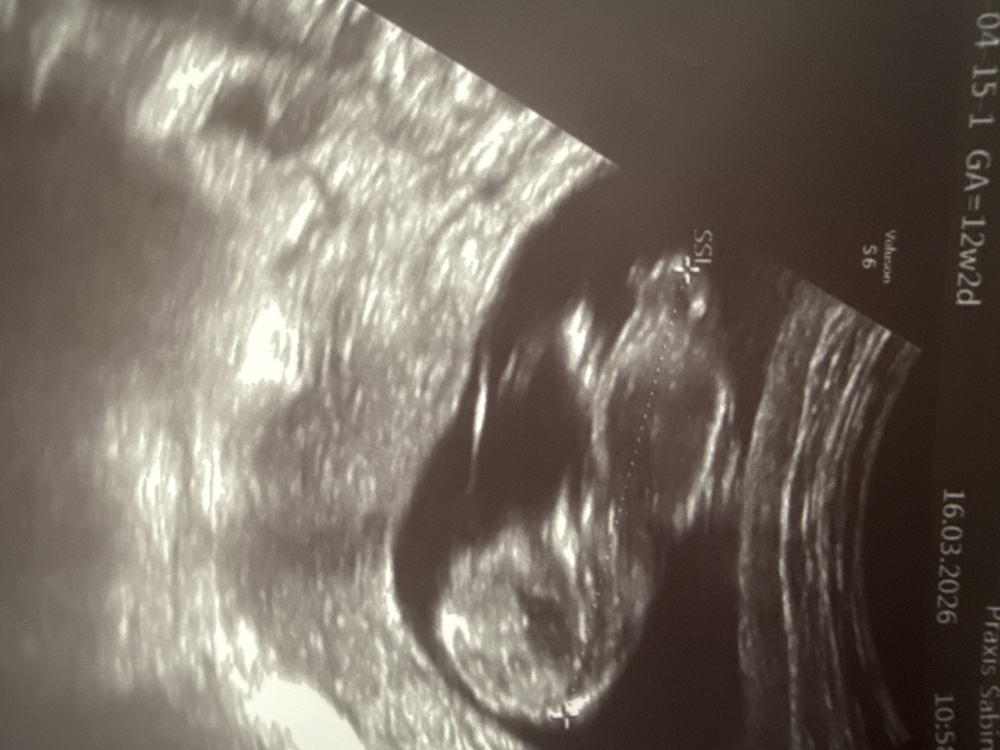

ich hatte mein Ersttrimesterscreening (Ssw 12+3) kann man hier den Nub erkennen und dann vielleicht auch das Geschlecht?

Würde mich so über eine Antwort freuen.

Vielen lieben Dank

Ich würde Mädchen raten.